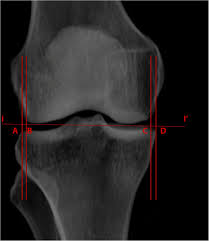

Knee Biomechanics Recon Orthobullets

Knee Biomechanics Recon Orthobullets from upload.orthobullets.com

The motions of the condyles include rocking, gliding and rotating. An articular cartilage injury, or chondral injury, may occur as a result of a pivot or twist on a bent knee, similar to the motion that can cause a meniscus tear. Of the six patients who had suffered an isolated fracture of their medial condyle, four of the patients had their fractures diagnosed on the first visit. Palpable as a hard, rounded bump to the inside of either knee joint, they are one of two condyles at the bottom of each leg bone, the other being the lateral femoral condyle. However, two of the patients had one or more fractures missed when they first presented. According to the hospital for special surgery, the medial femoral condyle is the inside of the knee, and health issues dealing with it can be treated. An imbalance of the muscles around the knee (some muscles are weaker than others.) overuse (repeated bending or twisting) of the knee joint, especially during sports. Palpable to either side of the knee joint when it is bent, they are known specifically as the medial and lateral femoral condyles.